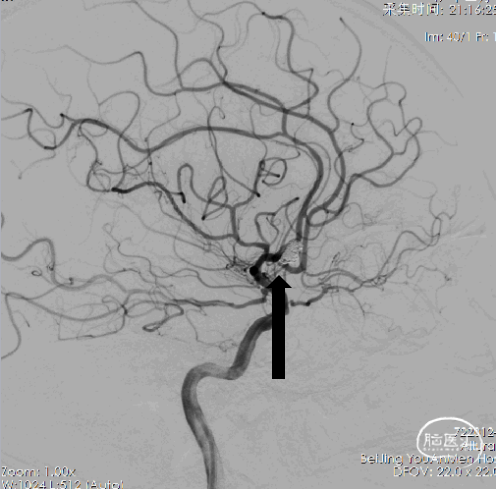

1、右侧颈内动脉造影提示双侧大脑前动脉显影,前交通动脉可见动脉瘤。

4、工作位测量:瘤颈长约3.94mm,瘤体大小约9.09×7.40mm,主瘤体上可见三个子瘤大小分别为:3.84×2.43mm、3.09×2.54mm、3.39×2.44mm。

14、栓塞后造影。

栓塞后正位造影